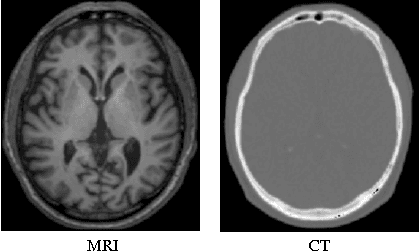

Abstract:Computed tomography (CT) is critical for various clinical applications, e.g., radiotherapy treatment planning and also PET attenuation correction. However, CT exposes radiation during acquisition, which may cause side effects to patients. Compared to CT, magnetic resonance imaging (MRI) is much safer and does not involve any radiations. Therefore, recently, researchers are greatly motivated to estimate CT image from its corresponding MR image of the same subject for the case of radiotherapy planning. In this paper, we propose a data-driven approach to address this challenging problem. Specifically, we train a fully convolutional network to generate CT given an MR image. To better model the nonlinear relationship from MRI to CT and to produce more realistic images, we propose to use the adversarial training strategy and an image gradient difference loss function. We further apply AutoContext Model to implement a context-aware generative adversarial network. Experimental results show that our method is accurate and robust for predicting CT images from MRI images, and also outperforms three state-of-the-art methods under comparison.